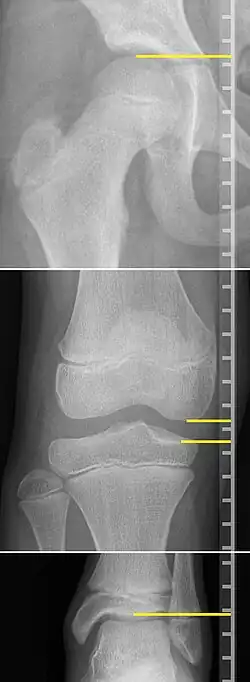

On X-rays, there is generally measurement of both the femur and the tibia, as well as both combined.[4] Various measuring points for these have been suggested, but a functional method is to measure the distances between joint surfaces:[4]

- Femur length: The superior aspect of the femoral head and the distal portion of the medial femoral condyle.

- Tibial length: The medial tibial plateau and the tibial plafond

- Orthoroentgenogram, which takes separate images of the hip, knee and ankle.

On X-rays, the length of the lower limb can be measured from the proximal end of femoral head to the center of the plafond of the distal tibia.[13]